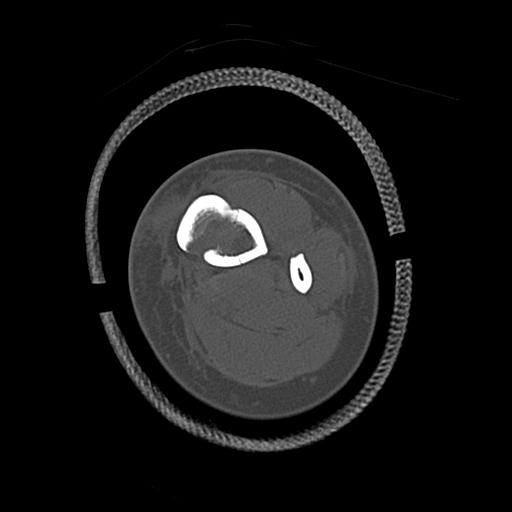

110286 2/17 股関節 2R 74歳女性 右人工骨頭

82084 1/14 1/20 股関節 2R 78歳男性 右人工骨頭

102811 1/13 股関節 2R 1/19 2R 80歳女性 右DHS